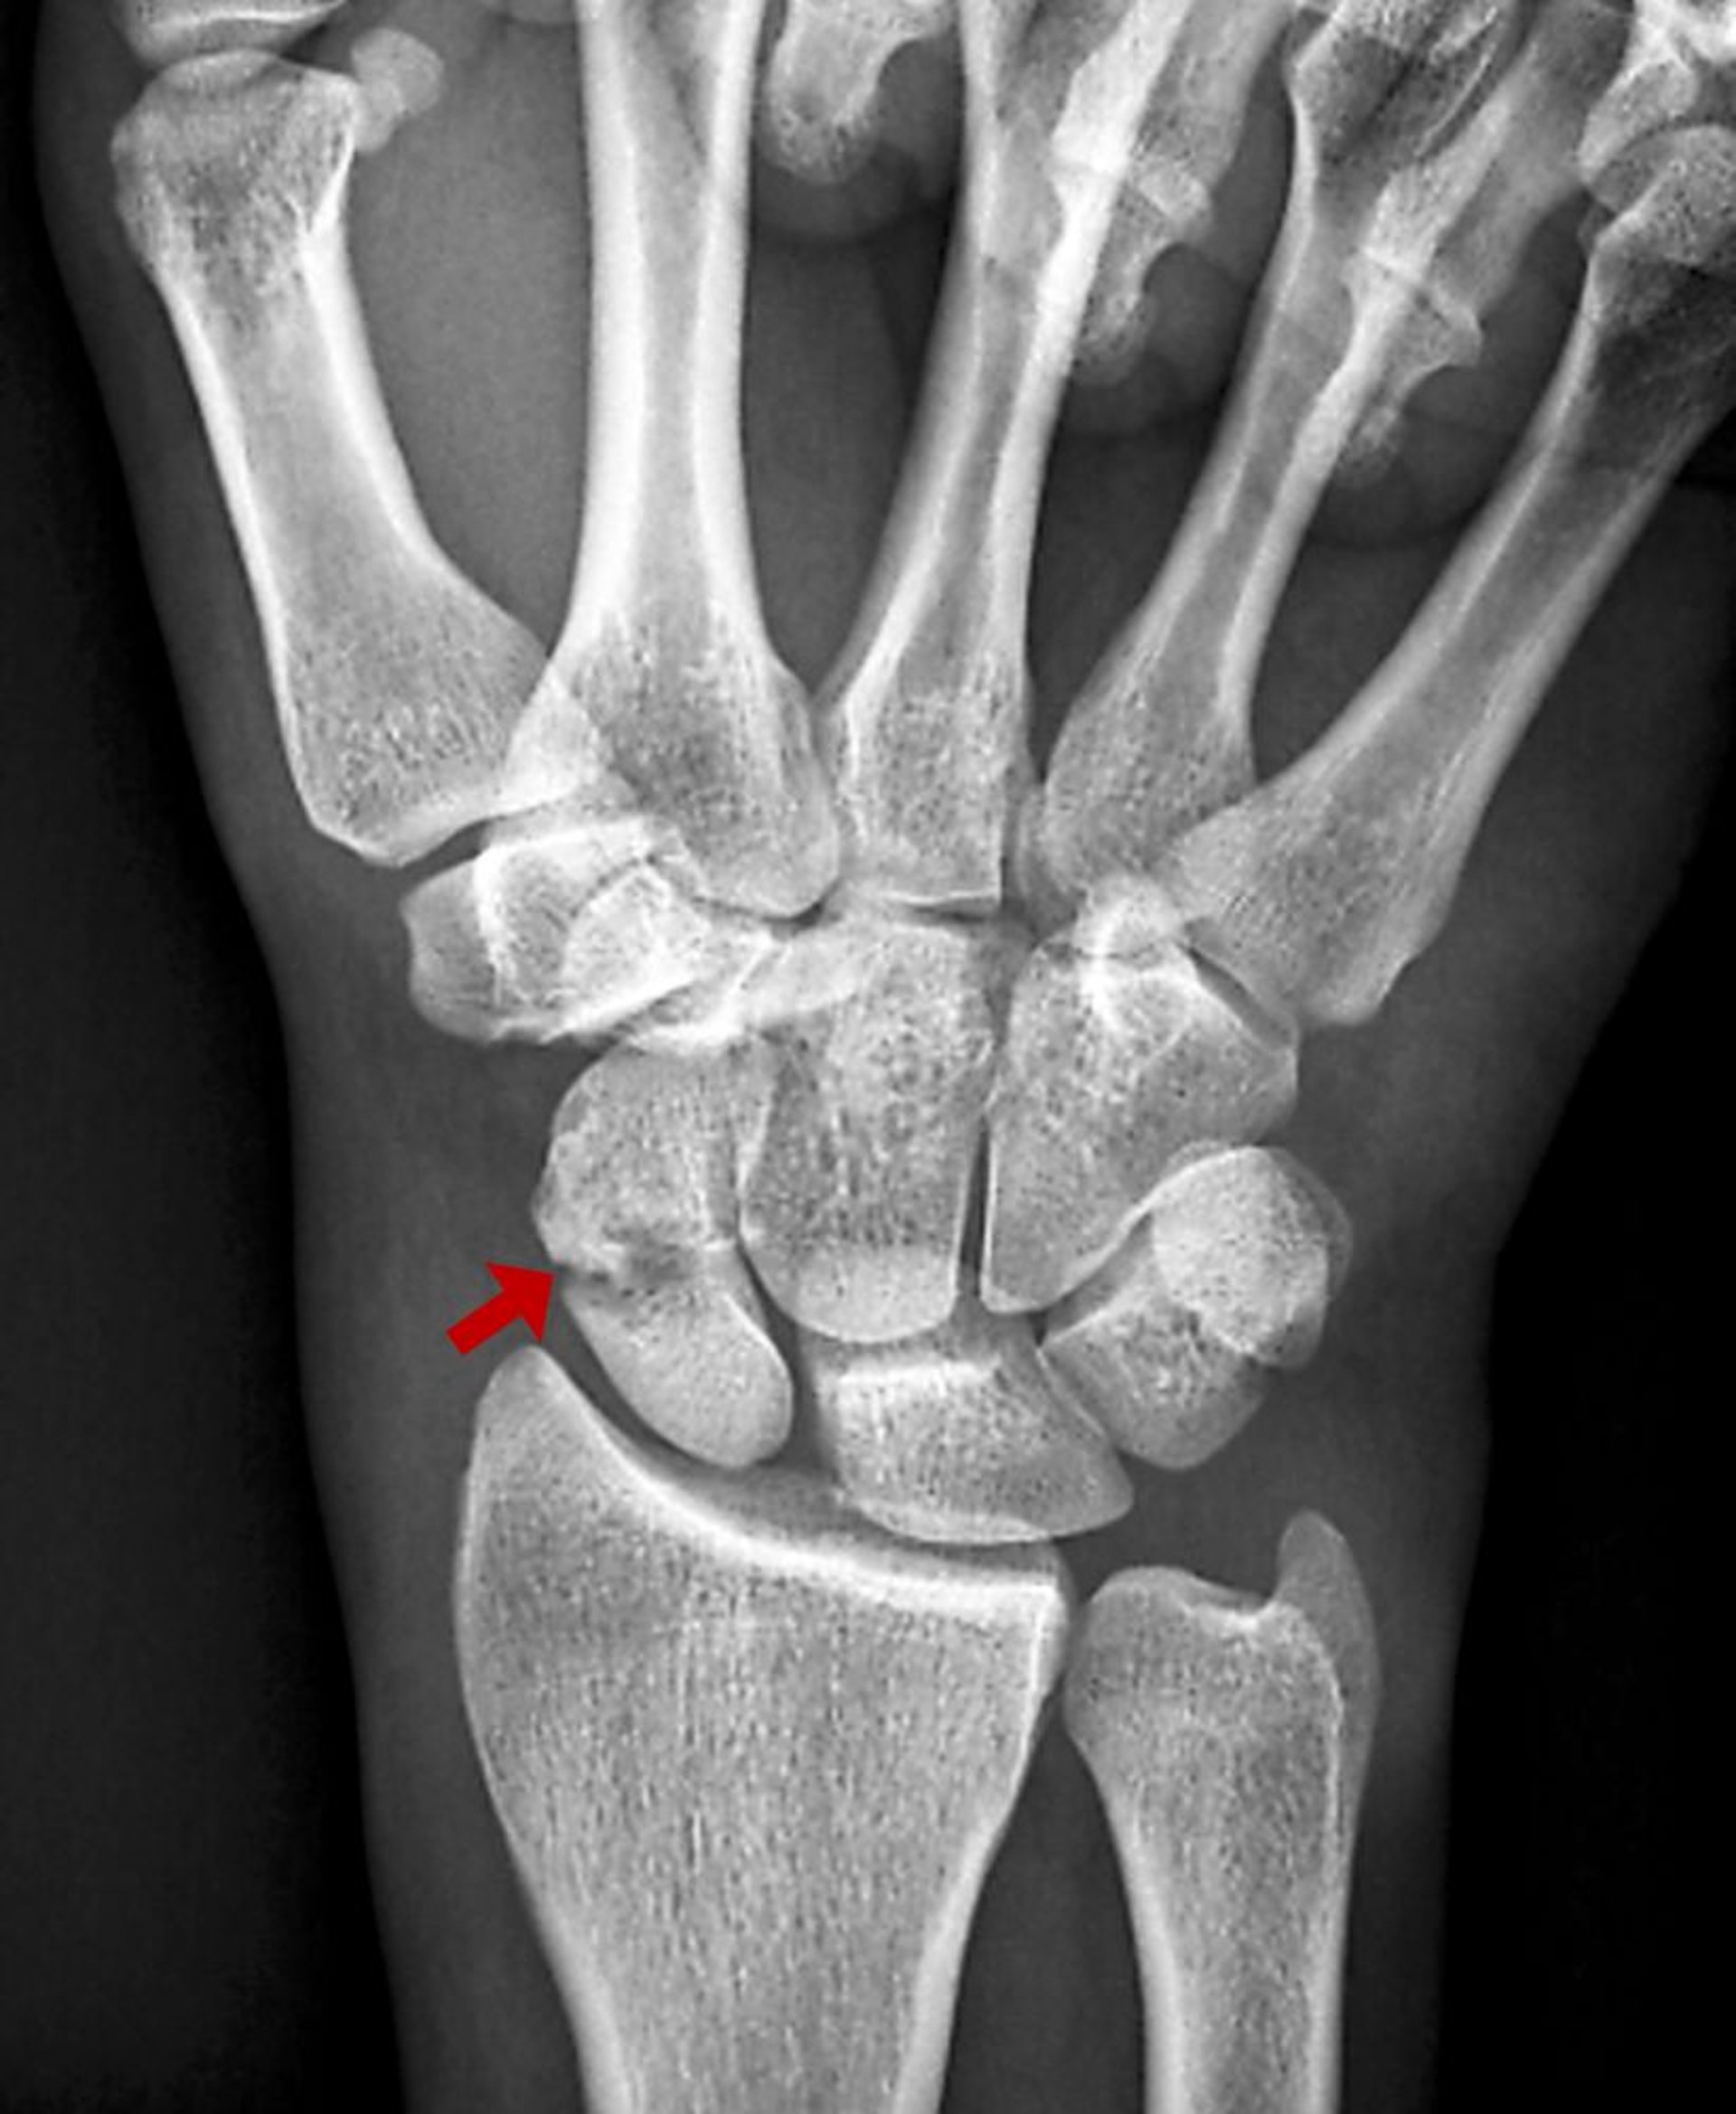

Fratura do escafoide

Essa fratura do escafoide é visível como uma radiotransparência na radiografia.